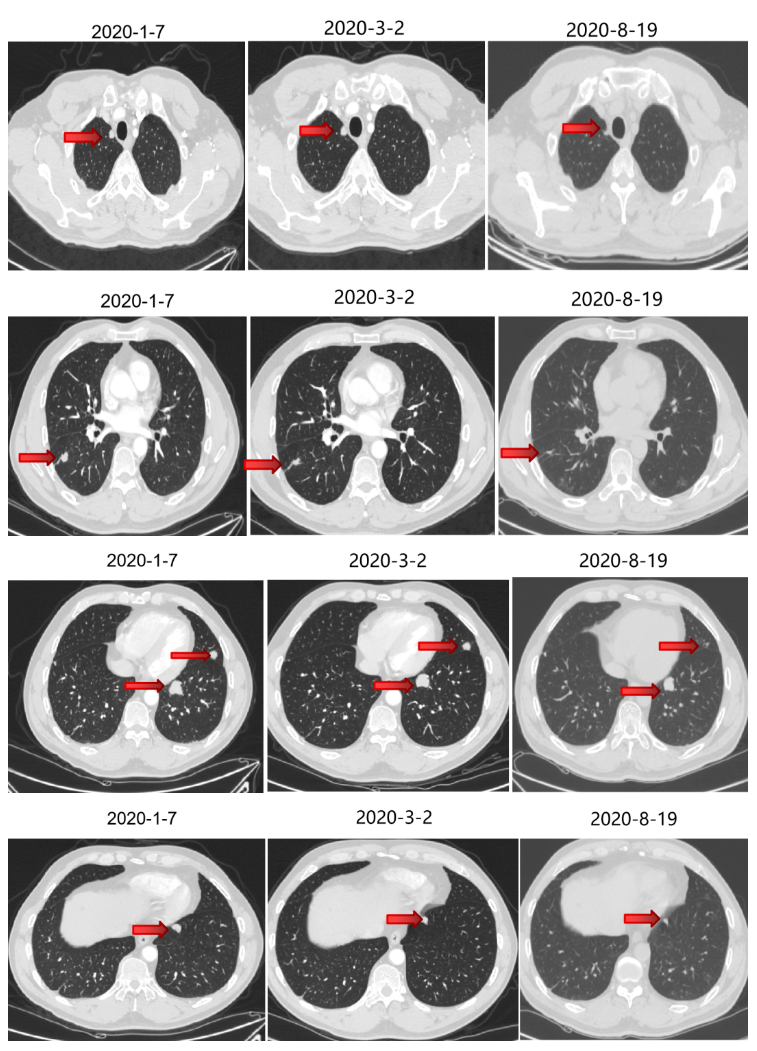

2020-1-7强化CT(我院)

2020-1-8至2020-3-4 行4周期西妥昔单抗+FOLFIRI方案治疗,第2周期起联合曲妥珠单抗治疗。

2020-3-23至2020-7-28 予5周期贝伐珠单抗+曲妥珠单抗+伊立替康+卡培他滨(因菌血症输液港取出换用卡培他滨,因皮疹反应不耐受换用贝伐珠单抗)。

二线治疗疗效评价:部分缩小,SD。

维持治疗

2020-8-19至2020-10-22 予4周期维持治疗:贝伐珠单抗+曲妥珠单抗+卡培他滨。

维持治疗疗效评价:部分略大,SD。